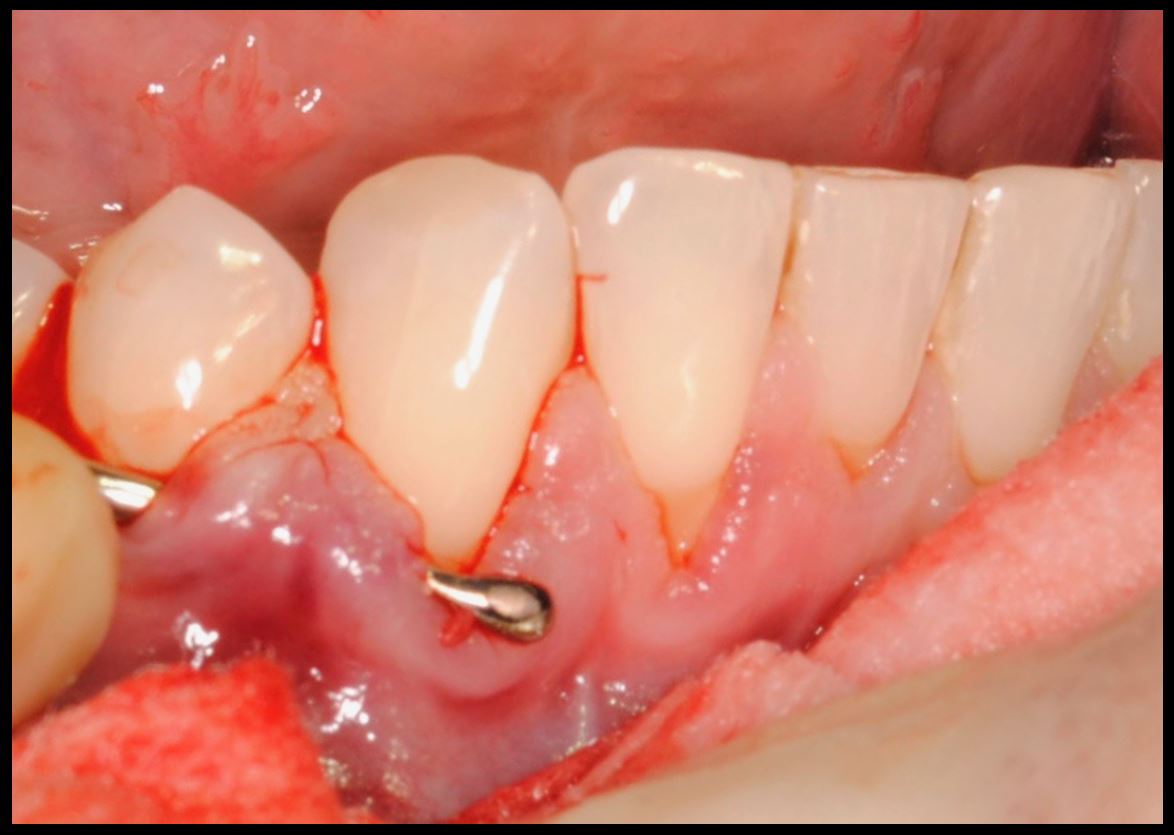

- Injerto de tejido conectivo libre desepitelizado de paladar + Tunelización

Fotografías del proceso: